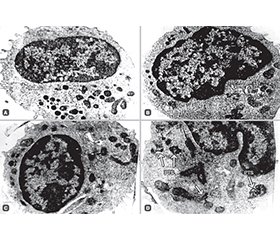

Актуальність. У хворих із вперше виявленим цукровим діабетом 2-го типу (ЦД2) спостерігається невелике, але статистично вірогідне зниження абсолютного числа природних клітин-кілерів (СD56+) у периферичній крові (ПК), особливо виражене при супутньому ожирінні. У зв’язку з вищевикладеним метою дослідження було подальше вивчення ролі NK-клітин у пацієнтів із вперше виявленим ЦД2, у тому числі ускладненим ожирінням. Для цього використовували комбінацію методів проточної цитометрії зі скануючою та трансмісійною електронною мікроскопією для визначення кількості та функції CD56+ клітин у ПК хворих із ЦД2. Матеріали та методи. Обстежено 144 особи обох статей із вперше виявленим ЦД2 віком 40–70 років, які не мали інших гострих та хронічних захворювань і раніше не приймали гіпоглікемічних препаратів. Контрольну групу становили 50 здорових людей із нормоглікемією віком 40–65 років, які не хворіли на COVID-19. Результати. Наші дослідження встановили, що в нелікованих пацієнтів із вперше діагностованим ЦД2 порівняно зі здоровими особами спостерігається дуже невелике статистично значуще зниження абсолютної кількості клітин CD56+ у ПК. При поєднанні проточної цитометрії (FACS методом) і супутніх трансмісійної та скануючої електронної мікроскопії у хворих на ЦД2 було виявлено значні зміни в ультраструктурі СD56+ клітин. Це вказує на зниження їхньої функції, а саме збільшення кількості клітин із більш гладенькою поверхнею клітинної мембрани, різке зменшення кількості азурофільних гранул у цитоплазмі, які вважаються основним продуцентом цитокінів і перфоринів, появу паралельно-трубчастих структур, біомаркерів зниження функцій клітин, порушення структури апарату Гольджі, гранулярного ендоплазматичного ретикулума та ін. Отримані дані свідчать про те, що у хворих на ЦД2, особливо на початковій стадії розвитку, спостерігається виражене послаблення функції NК-клітин, а отже, природного імунного захисту організму, й пояснюють підвищену схильність пацієнтів із діабетом до захворювання на різні віруси та інфекції, у тому числі COVID-19, а також тяжчий клінічний перебіг й підвищену смертність. Висновки. Проведені дослідження показують, що у хворих на початковій стадії ЦД2 спостерігається різке порушення субмікроскопічної організації CD56+ — найважливішого клітинного елемента природного імунітету, що свідчить про ослаблення функції природного імунного захисту. Це основна причина підвищеної чутливості хворих на діабет до інфікування різними патогенами, включаючи вірус SARS-CoV-2, а також більш тяжкого клінічного перебігу та підвищення рівня смертності.

Background. In patients with newly diagnosed type 2 diabetes mellitus (T2DM), a small but statistically significant decrease in absolute number of natural killer (NK) cells (CD56+) in the peripheral blood (PB) was found, especially pronounced with concomitant obesity. In connection with the above, one of the main aims of the present report was to further study the role of NK cells in patients with newly diagnosed T2DM, including those with obesity. For this purpose, a combination of flow cytometry methods with scanning and transmission electron microscopy was used to determine the number and function of CD56+ cells in the PB of patients with T2DM. Materials and methods. We examined 144 patients of both sexes with newly diagnosed T2DM aged 40–70 years who had no other acute or chronic diseases and had not previously taken any hypoglycemic drugs. The control group consisted of 50 healthy individuals with normoglycemia aged 40–65 years who had not COVID-19 disease. Results. Our studies have found that in untreated patients with newly diagnosed T2DM compared to healthy controls, there is a very small statistically significant decrease in the absolute number of CD56+ cells in the PB. When combining flow cytometry (FACS method), transmission and scanning electron microscopy in patients with T2DM, a significant change in the ultrastructure of CD56+ cells was revealed, indicating a decrease in their function (an increase in the number of cells with a smoother surface of the cell membrane, a sharp decrease in the number of azurophilic granules in the cytoplasm considered the main producer of cytokines and perforins, the appearance of parallel tubular structures, biomarkers of decreased cell function, a disruption of the Golgi apparatus structure, granular endoplasmic reticulum, etc.). The data obtained indicate that at the initial stage of T2DM development in humans, there is a pronounced weakening in the function of NK cells and, consequently, the natural immune defense of the body and explain the increased susceptibility of diabetics to various viruses and infections, including COVID-19, and also more severe clinical course and increased mortality. Conclusions. The conducted studies show that in patients with T2DM who are at the initial stage of T2DM, there is a sharp disturbance in the submicroscopic organization of CD56+ cells, the most important cellular element of natural immunity, which suggests a weakening of the function of natural immune defense. It is the main cause of increased sensitivity of diabetic patients to infection with various pathogens, including the SARS-CoV-2, as well as more severe clinical course and increased mortality rate.